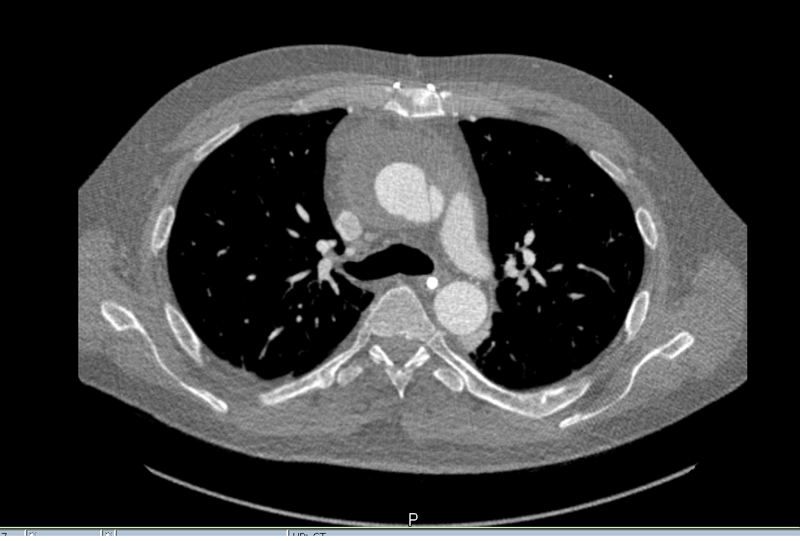

Contrast-enhanced CT is probably the most widely used imaging technique in the diagnosis of aortic dissection. It provides fast image acquisition and processing with the ability to obtain complete 3D datasets of the entire aorta. However, CT exposes patients to ionising radiation and to contrast agents that may cause allergic reactions or renal failure [5, 46]. According to the IRAD study, prompt chest CT scan as the initial test is associated with the quickest diagnostic time [44]. Moreover, the important findings of imaging, such as extent of the dissection and regurgitation, size of the false and true lumen, involvement of the arterial branches, or presence of hematoma, can support the management (fig. 3).

Figure 3 Computed tomography scan of type A dissection with haematoma.